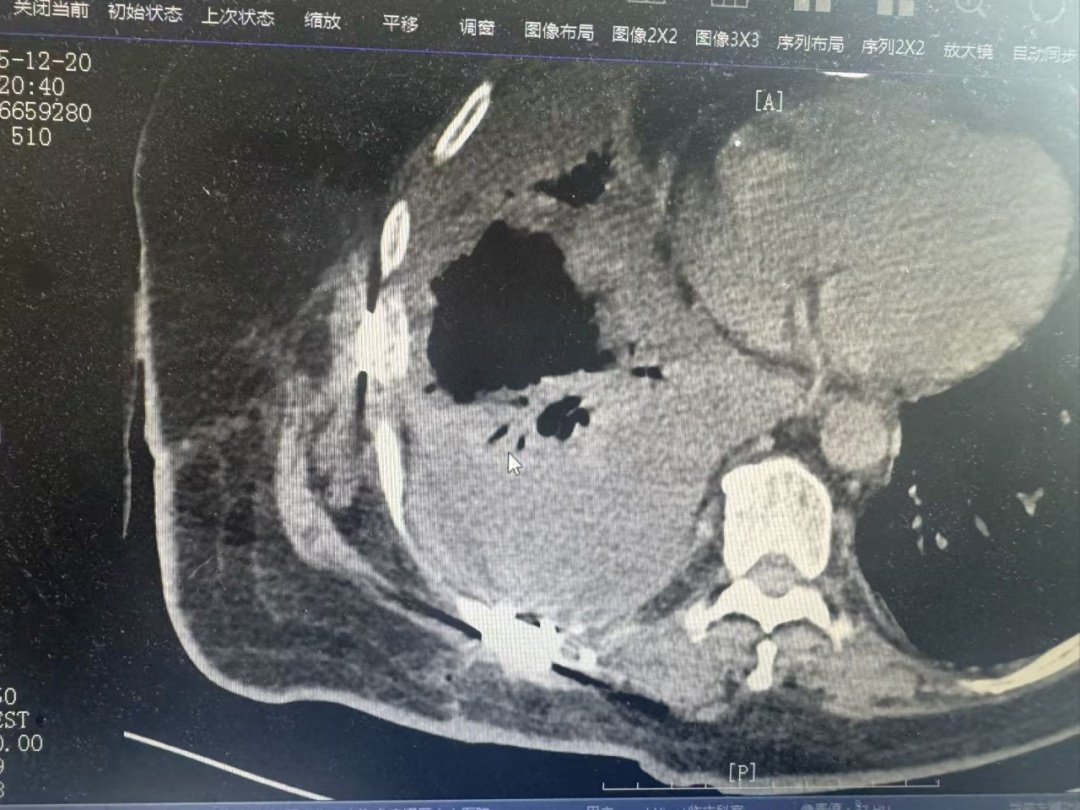

张先生因严重胸部外伤导致“连枷胸”,经肋骨内固定手术后一度恢复平稳。然而,就在出院前的复查中发现了一个“大麻烦”:他的胸腔内仍存在大量积液,且因病程较长已形成“包裹性”改变。

更棘手的是,张先生胸壁厚度较常人更厚,达8厘米。这意味着,如果使用传统的穿刺方法,医生就如同在厚厚的“门板”后摸索一个“小水泡”,极易“迷路”——刺不准、排不净,甚至可能损伤重要血管和脏器,风险极高。

术中,超声医学科吴涛主治医师仔细扫描,精准锁定积液范围最宽、最适合穿刺的区域,并在体表做出标记,精确测量进针路径与深度。随后,胸外科宋嘉文医师接过“接力棒”,在超声影像的实时“导航”下,将穿刺针稳稳地沿着预定路径送入,精准无误地直达“目标水囊”。一次成功!约800毫升浑浊的积液被顺利引出,患者术后胸闷气促症状得以迅速缓解。

术后复查显示,张先生的胸腔积液基本消失,被压迫的肺部完全复张。在胸外科团队的后续精心治疗与护理下,恢复良好,顺利出院。出院前,他和家人特意为宋嘉文和吴涛两位医生送上锦旗。